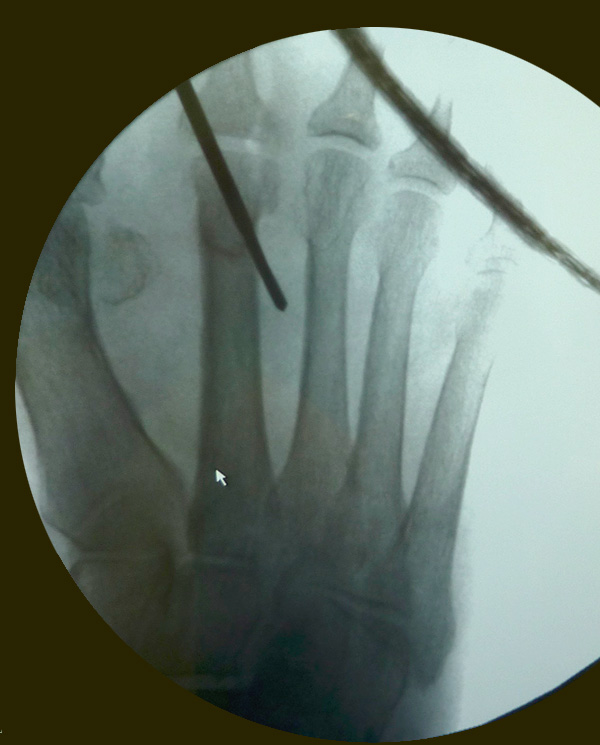

• Röntgenaufnahmen des Fuß in drei Ebenen im Stehen (siehe Abb. 2).

Zum Lesen der Bildbeschreibung und zur Vollansicht bitte das Bild anklicken. Bild: M. Walther.

• Unter Durchleuchtungskontrolle Positionieren der Shannon-Fräse mit 20 mm langem und 2 mm dicken Fräsenkopf in 45° Neigung an den Hals des Metatarsale (siehe Abbildung 3 a und b).

• Verschieben der Fräsenspitze um wenige Millimeter nach proximal.

• Röntgenkontrolle, um die korrekte Position von Fräsenspitze bzw. Osteotomieebene an der distalen Diaphyse des Metatarsale-Knochens zu bestätigen (Abbildung 3 c).

Zum Lesen der Bildbeschreibung und zur Vollansicht bitte die Bilder anklicken. Bilder: A. Mehlhorn.